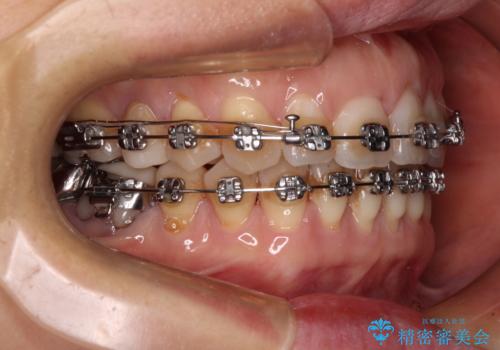

正中のズレと飛び出した前歯を改善 メタルブラケットでの抜歯矯正

- 飛び出した上顎前歯と正中のズレを気にして来院された患者様です。

上顎正中が右側にずれていたので、むし歯が酷く抜歯が必要な左側臼歯を抜歯して正中を改善することとしました。

左下には新しいセラミックのブリッジが装着されていたため、ブリッジを壊さずに改善できるところまで咬み合わせを改善していくこととしました。

右上小臼歯は銀歯が装着されており、ワイヤー矯正の装置が装着できないため、事前に仮歯に変えてから矯正治療を行い、その後オールセラミッククラウンにて補綴治療を行いました。